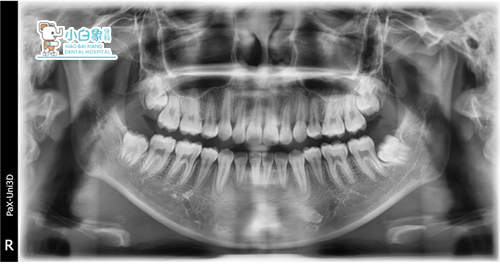

治疗后X线片

治疗前X线片

X线见21根间高密度异常影像

见18、28、38、48恒牙